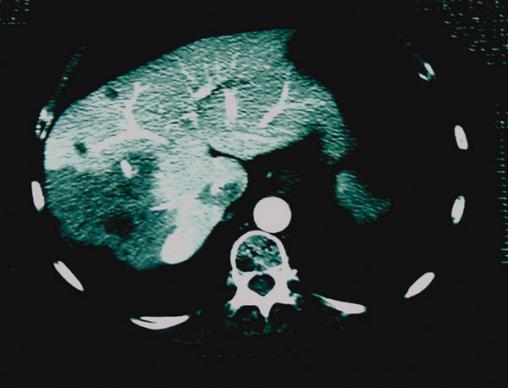

La Revue du Praticien - Jacques Belghiti Image unique hypodense avec un halo hypervasculaire. Sur le porto-scanner, visualisation de 3 autres lésions.